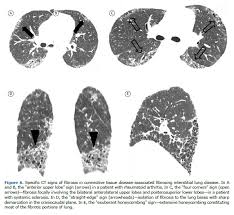

Sarcoidosis interstitial lung disease. Bilateral hilar adenopathy. When sarcoidosis causes scaring in the lungs it may be referred to as Interstitial Lung Disease ILD. Sarcoidosis a form of interstitial lung disease is a rare disease characterized by the discrete accumulation of inflammatory cells and matrix proteins granulomas in different parts of the body typically the lungs pulmonary sarcoidosis.

Interstitial lung disease is an umbrella term used to define a complex group of pulmonary diseases including sarcoidosis and idiopathic pulmonary fibrosis. Sarcoidosis is a rare disease caused by inflammation. Interstitial lung diseases ILDs result from damage to the alveoli air sacs leading to inflammation and fibrosis of the interstitium tissue wall between the.

Interstitial Lung Disease ILD and Sarcoidosis Program Interstitial Lung Disease ILD and Sarcoidosis Program. Sarcoidosis is a granulomatous disease of unknown cause occurs worldwide and has a highly variable prevalence. It causes small lumps of inflammatory cells in the lungs.

This disease is difficult to pin down in so many ways understanding if you have ILD as a result of sarcoidosis is just one of them. Sarcoidosis is a granulomatous disease of unknown cause occurs worldwide and has a highly variable prevalence. 1 Sarcoidosis affects only around 1-36 people in 100000 each year where 20 of these people develop ILD. At least 5 of cases include pulmonary arterial hypertension. 1 In this form of ILD scarring of the lung tissue might develop. Sarcoidosis is a rare disease caused by inflammation. It causes small lumps of inflammatory cells in the lungs. 1202 ILDdiffuse parenchymal lung diseases DPLD of known origin. The interstitial lung diseases ILDs are characterised by dyspnoea on exertion exercise-induced hypoxaemia reduced skeletal muscle function and exercise intolerance.

Sarcoidosis a form of interstitial lung disease is a rare disease characterized by the discrete accumulation of inflammatory cells and matrix proteins granulomas in different parts of the body typically the lungs pulmonary sarcoidosis. Overtime this can lead to permanent scarring or thickening of the organ tissue also called fibrosis. Sarcoidosis is a multisystem granulomatous disorder of unknown etiology that affects individuals worldwide and is characterized pathologically by the presence of noncaseating granulomas in involved organs. Interstitial lung disease ILD describes a broad category of. In this form of ILD scarring of the lung tissue might develop. Sarcoidosis affects only around 1-36 people in 100000 each year where 20 of these people develop ILD. Interstitial lung disease is an umbrella term used to define a complex group of pulmonary diseases including sarcoidosis and idiopathic pulmonary fibrosis.